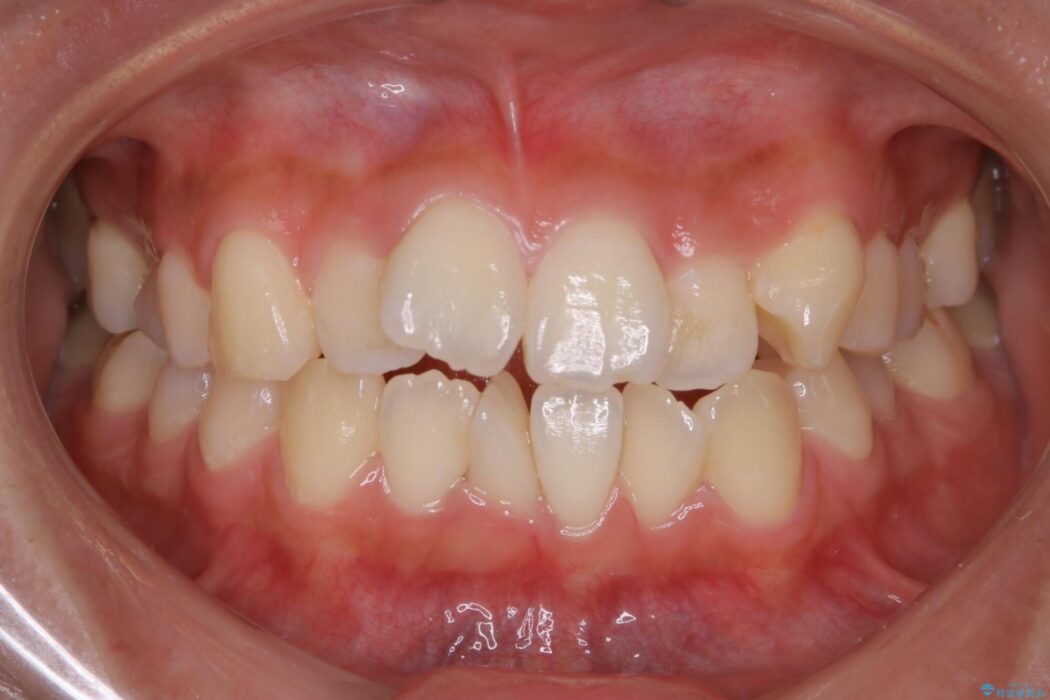

上下前歯のねじれなどで生じている歯列のガタつきをなおしたいとのことで来院されました。

特に前歯部分に90度近く捻転した歯、斜めに生えている歯などによる歯列のがたつき、正中のズレが目立っていました。

奥歯から遠心移動とディスティング(歯の側面を僅かに削る)を行うことで歯列を整えるスペースを確保し、患者様のご要望からインビザライン装置での矯正を計画しました。